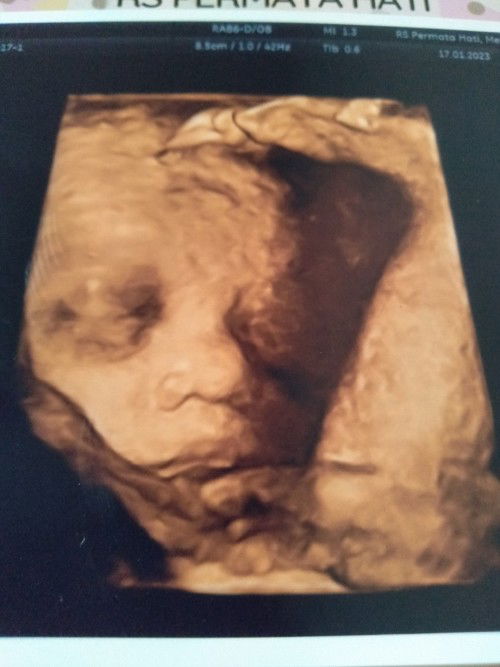

Hasil USG 28 week 3 day

Alhamdulillah liat perkemabangan dedek Utun sehat. JK girl nih bund. Cmn worry karna BBj masih 1100 gram. Mnurut aplikasi udh normal tpi kata dokter kurang😥 Cara lain atasi kurang BBj selain konsumsi eskrim apa sih bund🙏 sharing bund😁#bantusharing #seriusnanya